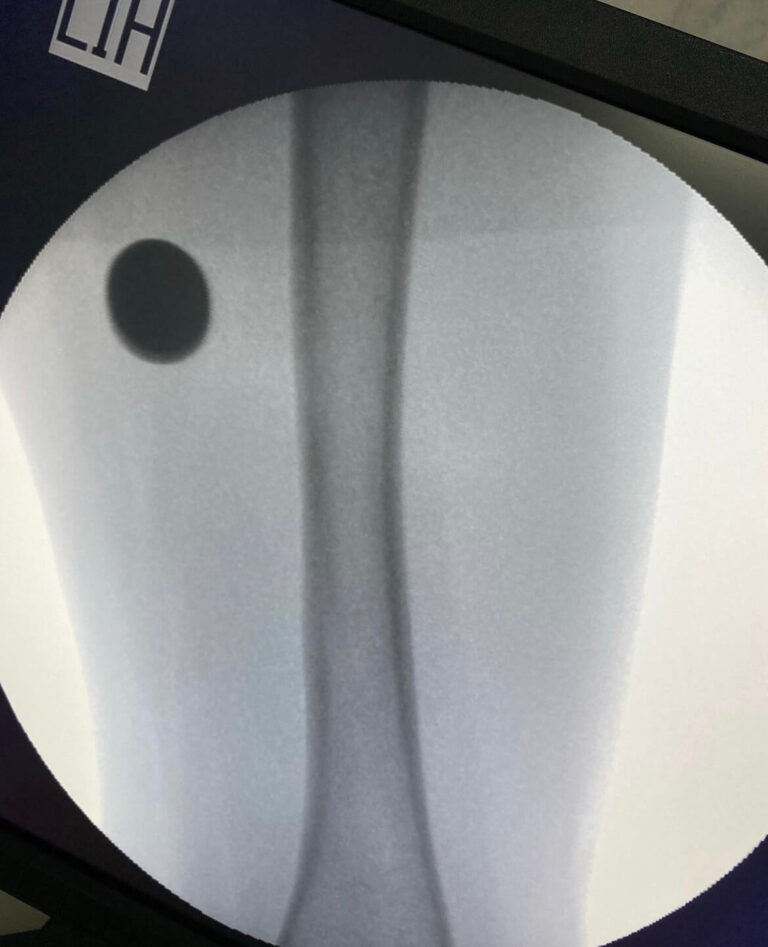

Современная сложная реконструктивная ортопедия в

мц «ЛАДИСТЕН КЛИНИК» город Киев Украина